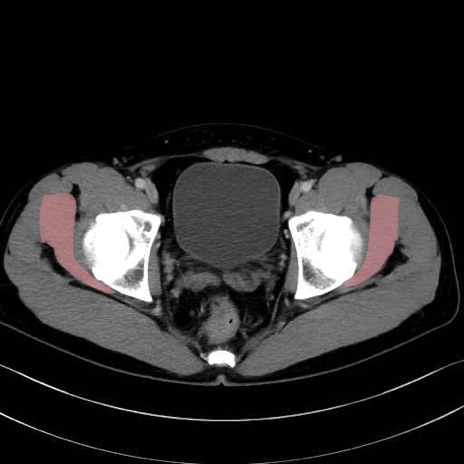

小殿筋 (Gluteus minimus)